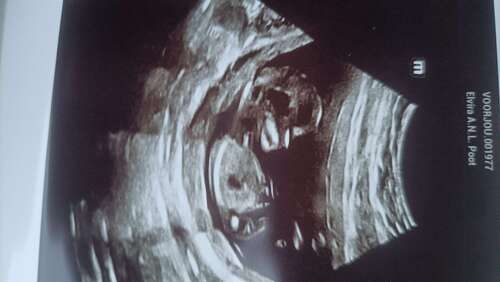

Super spannend Zie foto echo was leeg veder niets datze zeiden mis komt dit nog of zit het nu aan de zijkant dus nu 🤞

De echo was inwendig. Ja kan nu niks anders dan hopen

inmiddels bijna14 weken🥰